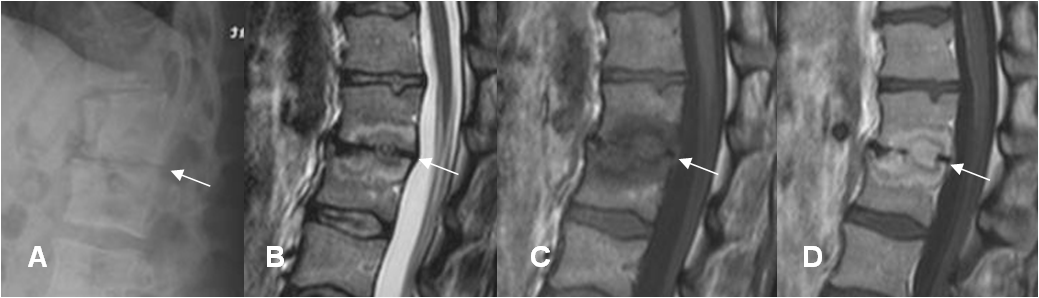

Con la RM el espacio intervertebral puede ser normal o disminuido. Puede encontrarse aumento, ante la formación de un absceso. (31).

El disco es isointenso en T1, hiperintenso en T2 y con realce periférico del contraste. La ausencia de la hendidura discal es muy sugestiva de infección, sobre todo en el segmento lumbar. (31).

La destrucción y el colapso vertebral, se caracteriza por ser hipointenso en T1 e hiperintenso en T2 y que realza con del contraste. (33). (Fig 139).

Otro signo característico de la espondilodisquitis, es la extensión paraespinal y epidural, de los cambios inflamatorios. La ausencia de estos hallazgos, excluyen la infección. (31, 57). (Fig 140 A y B).

Fig 139. Espondilodisquitis.

A: Rx lateral. Disminución en la amplitud del espacio intervertebral, por espondilodisquitis.

B: RM sagital en T2, C: RM sagital en T1 y D: RM sagital en T1 con contraste. Adicional a la disminución del espacio, se aprecia alteración en la señal de las placas terminales, las cuales son hiperintensas en T2, hipointensas en T1 y realzan con el contraste.